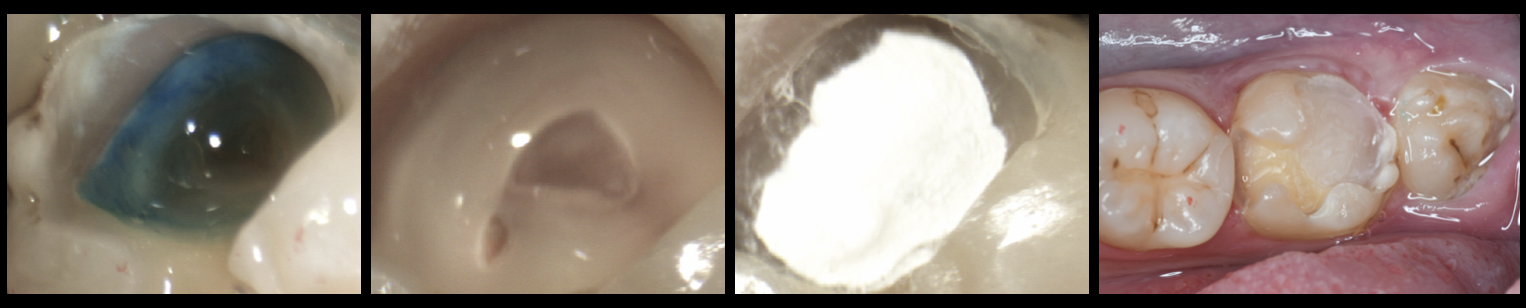

(左下7)歯の神経(歯髄)を保存したケース:(Vital Pulp Therapy:歯髄温存療法)をおこないCEREC:セレックを用いた即日オールセラミック修復をおこなったケース!!(自費診療!!)

(左下6)虫歯はダイレクトボンディングにて修復!!

写真左・中左・中右:う蝕検知液をもちい虫歯:う蝕を除去除去していくと歯の神経(歯髄)まで到達。ダイヤモンドチップにて歯の神経(歯髄)を切断。切断面の確認。生理食塩水にて止血後、MTAにて直接覆髄。メガボンド2(クラレノリタケデンタル)をもちいてコンポジットレジンにて封鎖。

写真右:封鎖後、形成を行い、セレックプライムスキャンを用いて光学印象を行い、

セラミック修復物の製作(VITA MarkⅡ 2M1C)

写真左:術後の口腔内:レジンセメント:パナビアV5クリア にてセット

ここまで全て即日でおこなっております(治療1回)